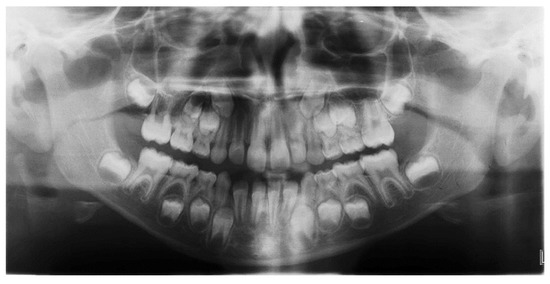

3D Printed Customized Facemask for Maxillary Protraction in the Early Treatment of a Class III Malocclusion: Proof-of-Concept Clinical Case

2. Materials and Methods

3. Results

| Variables | Normal Values | Pretreatment | Posttreatment |

|---|---|---|---|

| Angular degrees | |||

| SNA | 82 | 87.7 | 89.6 |

| SNB | 80 | 85.3 | 83.5 |

| ANB | 2 | 2.5 | 6.2 |

| SN to Palatal Plane | 8 | 9.6 | 9.6 |

| SN to Mand. Plane | 32 | 33.3 | 33.5 |

| Co-Go-Me | 125 | 136.1 | 130 |

| Upper Inc. to Palatal Pl | 110 | 119 | 113.6 |

| Lower Inc. to Mand. Pl. | 90 | 87.5 | 91.8 |

| Linear, mm | |||

| Wits | 0 | −6.3 | −3.1 |

| Overjet | 2.5 | 0.4 | 2.7 |

| Overbite | 2.5 | 1.1 | 3.6 |